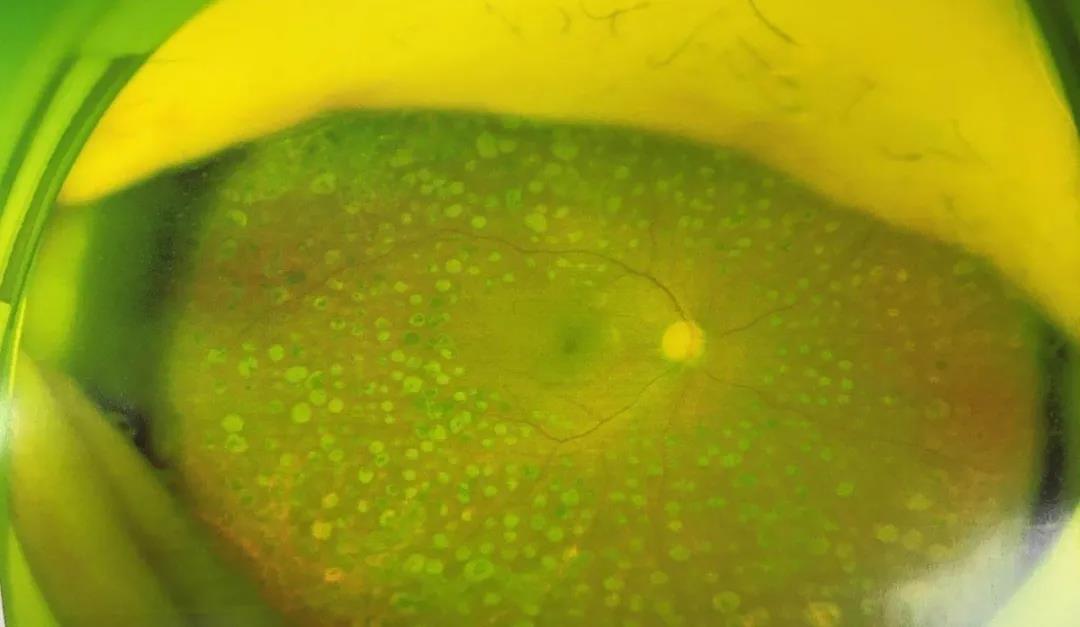

术后眼底对比▼

李军院长根据赵阿姨的检查结果,果断为其制定了手术方案,并于3月11日实施了手术。患者术后恢复良好,不仅修复了出血的视网膜,还一并治好了右眼白内障,复查时,右眼视力达到0.8,在视觉质量上得到了很大的提升。